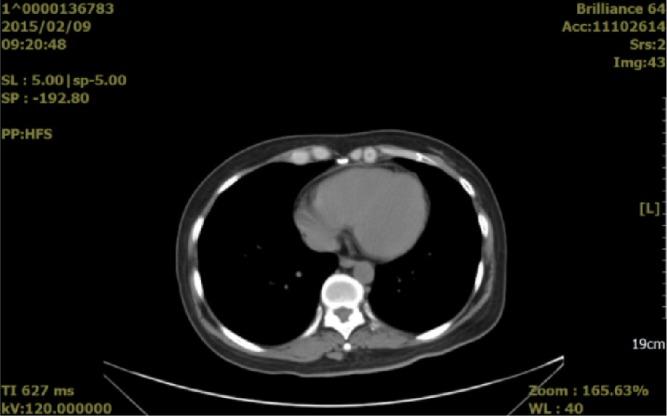

Malignant pericardial effusion (MPCE) is a common complication of advanced malignant tumors, and interferes severely with patient prognosis and quality of life. The standard treatment for this complication is intracavitary perfusion of chemotherapeutic drugs, which is limited by unsatisfactory therapeutic effects and serious adverse events. We report a patient with MPCE who was treated with bevacizumab by pericardial perfusion, resulting in a complete response. This case supports the use of intrapericardial bevacizumab as a potential treatment for MPCE.

恶性心包积液(MPCE)是晚期恶性肿瘤的常见并发症,严重影响患者预后和生活质量。该并发症的标准治疗方法是腔内灌注化疗药物,但存在治疗效果不理想和严重不良事件的限制。我们报告了1例MPCE患者,通过心包灌注贝伐单抗进行治疗,取得了完全缓解。该病例支持心包内注射贝伐单抗作为MPCE的一种潜在治疗方法。